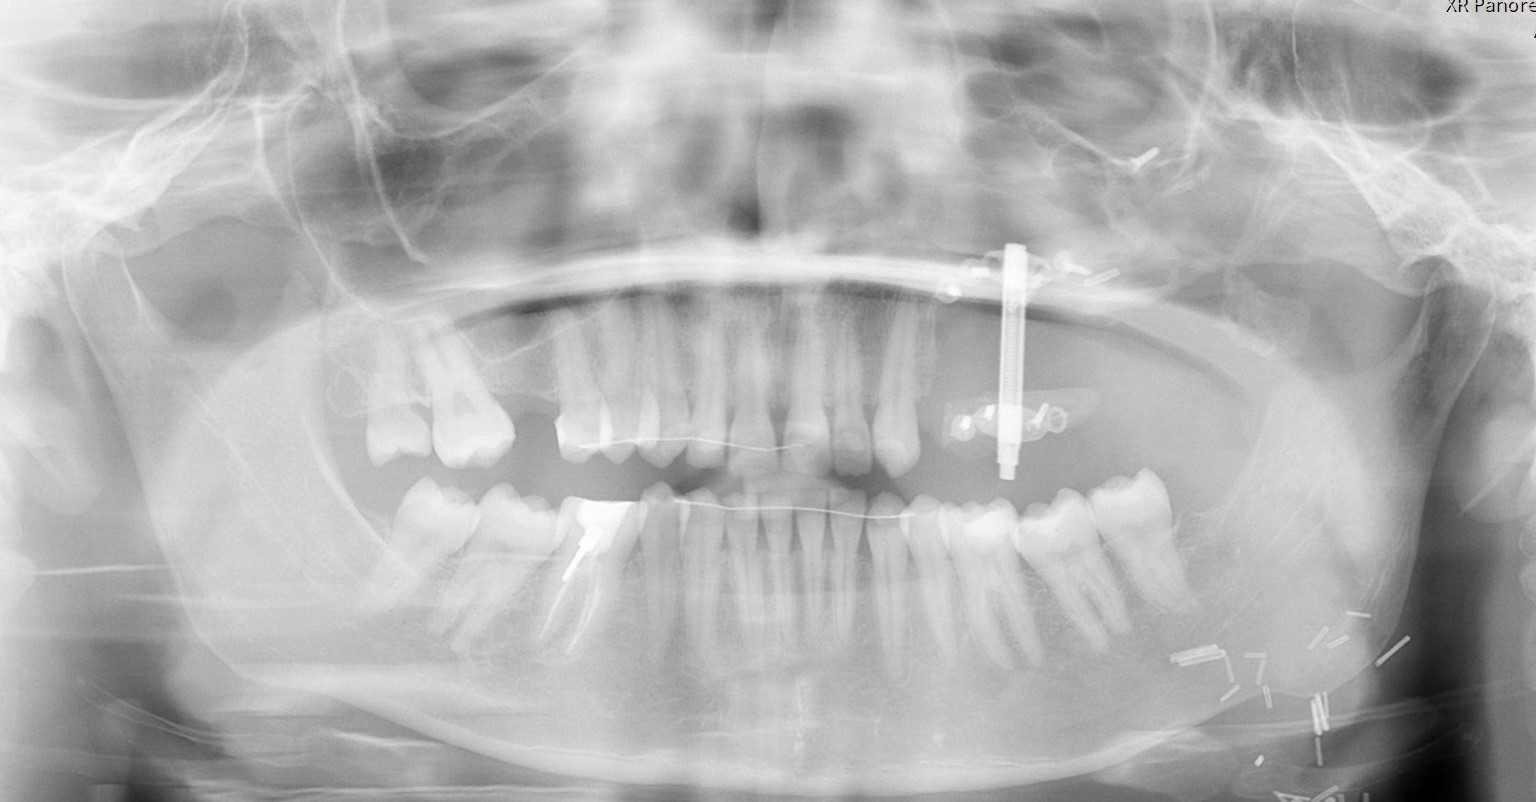

A distraction device was placed after a latency period of 7 days. The fibula graft underwent vertical distraction over a 6-week period at a rate of 0.5 mm twice daily, achieving approximately 12 mm of vertical bone gain. Radiographic evaluation (Image 1 and 2) showed successful osteogenesis without complications. After a 3-month consolidation period, dental implants were placed into the distracted fibula segment.

Fig 1: Pre-distraction Radiograph: Initial placement of the fibula free flap post maxillary resection.